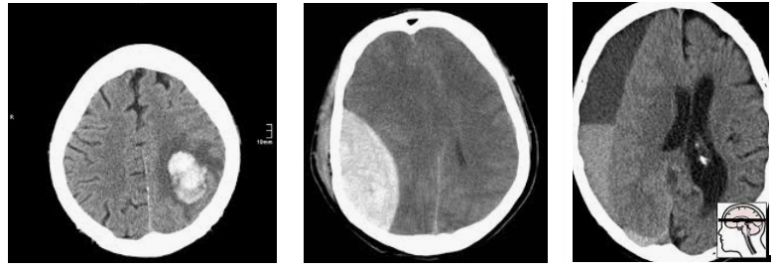

最近,一个新的大型CT脑扫描数据集被发布,其目的是训练模型以检测颅内出血。

那么我们如何处理多重假设检验呢?这一切都归结于问题的原因,即数据。Epi101告诉我们,任何测试集都是目标总体的一个有偏差的版本。在这种情况下,目标人群是“所有CT头部成像的患者,有或无颅内出血”。让我们来看看这种偏见是如何产生的,举一个小的数据集示例:

在这一人群中,我们有相当合理的“临床”病例组合。3例脑内出血(可能与高血压或中风有关),2例创伤性出血。

现在让我们对这个群体进行抽样,以构建我们的测试集:

随机地,我们抽样得到的大部分是轴外出血。在这项测试中表现良好的模型不一定能在真实的患者身上发挥同样的效果。事实上,你可能期望一个擅长轴外出血而牺牲脑内出血的模型获胜。